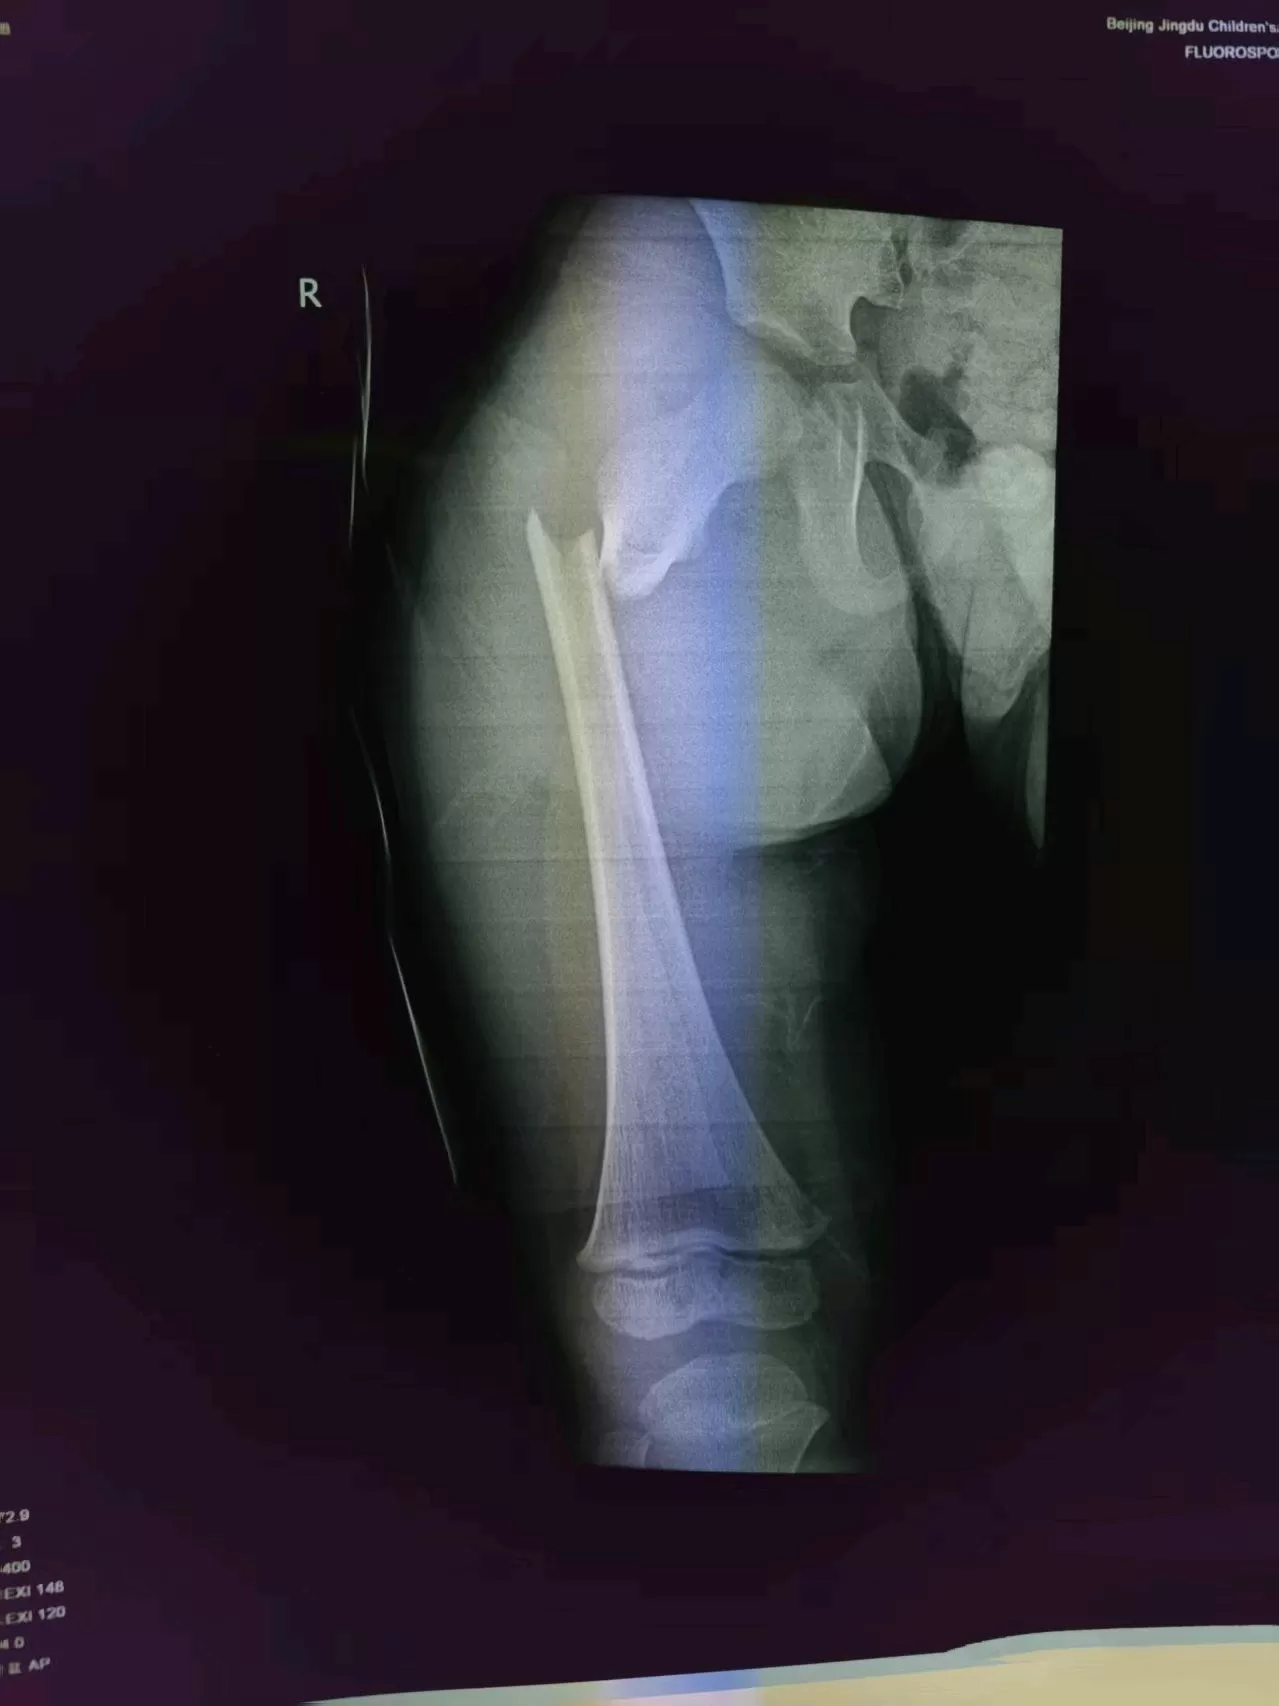

When the early morning sun of June 19th just streamed through the kindergarten gate, Ms. Li (pseudonym) had no idea that a tiny oversight—leaving the electric bike key (unremoved)—would plunge her 3-year-old son Lele into a bone crisis. As the child got off the bike, he accidentally touched the switch; the out-of-control electric bike dragged him to the ground, and his right leg was run over by the wheel. "The thigh bone is broken and requires surgery," the emergency doctor’s words pierced her heart like an ice pick.

"We can operate today," Dr. Chou touched Lele’s forehead with warm fingertips. "The child’s injury is suitable for elastic intramedullary nailing. We can fix it with minimally invasive surgery—no large incision, short procedure time, and quick recovery." He opened the medical record and explained the surgery to the mother, circling the fracture site with a colored pen: "It’s like threading an 'elastic shoelace' through the bone, fixing it from the marrow. The wound will only be two pinholes."

At 4:40 p.m. that day, Lele was wheeled into the operating room. Dr. Chou Xiaobing’s team was already prepared—this "precision reduction with elastic intramedullary nails" is their signature technique. Over the past decade, it has been used in over 4,000 surgeries, compressing the time for complex pediatric fracture procedures to 30 minutes with an error margin controlled within 1 millimeter.

While Ms. Li clutched her husband’s hand, trembling outside the operating room, real-time monitoring on the screen showed that intraoperative radiation exposure was 70% lower than in traditional surgeries—a low-dose imaging method unique to children’s hospitals. The two incisions, each smaller than 2 centimeters, barely bled—this is the "bloodless surgical field" standard of the Pediatric Orthopedics Department at Jingdu Children’s Hospital. At 5:30 p.m., Dr. Chou walked out of the operating room: "The bone is aligned perfectly. The child can take a sip of water once he wakes up."